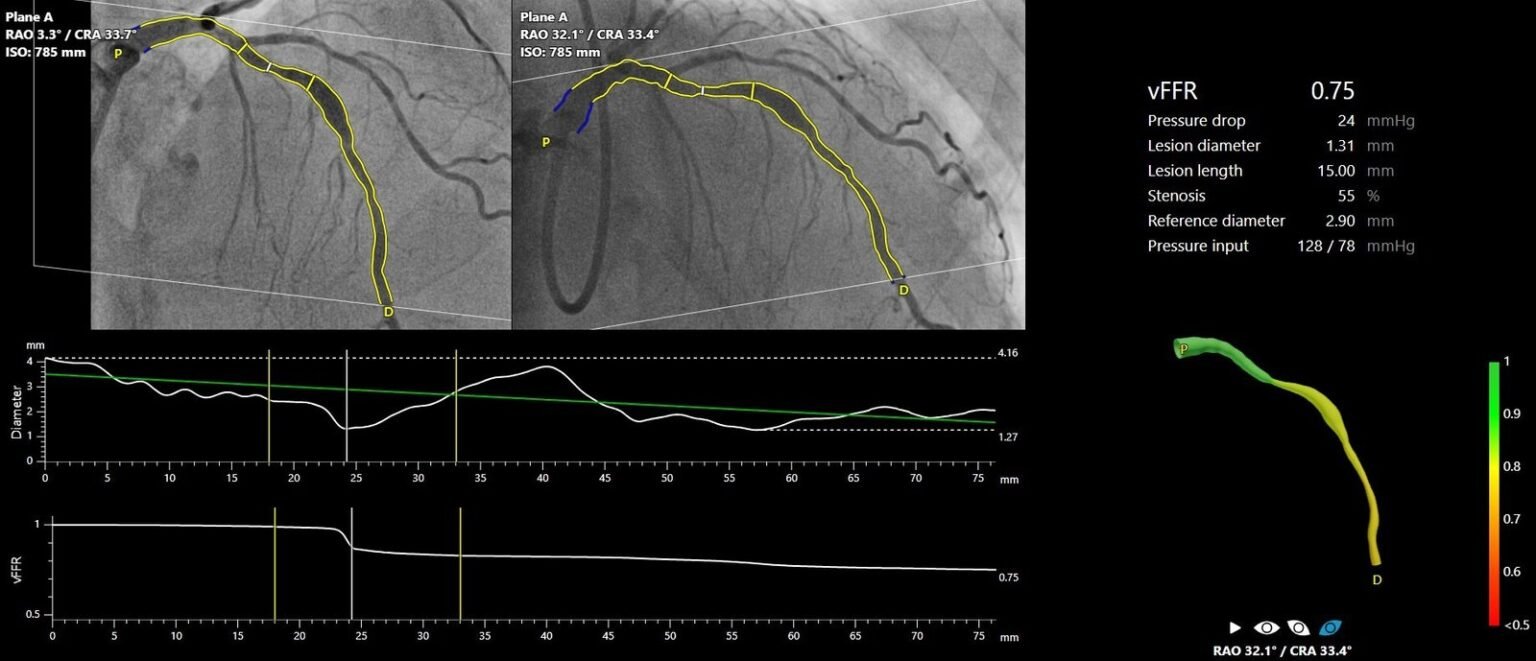

FAST III war eine vom Prüfarzt initiierte, offene, multizentrische, randomisierte Studie, in der eine vFFR-geführte mit einer FFR-geführten Koronarrevaskularisation bei 2235 Patienten mit intermediären Koronarläsionen (definiert als 30-80%ige Stenose durch visuelle Beurteilung oder QCA) verglichen wurde. Intermediäre Läsionen wurden physiologisch anhand von vFFR oder FFR auf der Tischseite beurteilt und behandelt, wenn vFFR oder FFR ≤0,80 waren. Der primäre Endpunkt war ein Kompositum aus allen Todesursachen, einem Myokardinfarkt oder einer Revaskularisierung 1 Jahr nach der Randomisierung.

„Die Ergebnisse von FAST III bestätigen die Sicherheit und Machbarkeit des Online-Einsatzes der vFFR als einfaches, minimal-invasives Instrument zur Anleitung der Revaskularisation bei Patienten mit intermediären Koronararterienläsionen, die eine physiologische Beurteilung der Läsion benötigen. Die Technologie hat das Potenzial, den Einsatz der Physiologie zu verstärken, was die Prognose von Patienten verbessern könnte, bei denen die Entscheidung zur Revaskularisierung intermediärer Koronararterienläsionen immer noch weitgehend auf Augenmaß beruht. Der Einsatz der vFFR macht Führungskatheter, invasive Koronararterieninstrumente und hyperämische Wirkstoffe überflüssig, die mit Risiken und Unannehmlichkeiten für den Patienten verbunden sind“, so Dr. Joost Daemen.